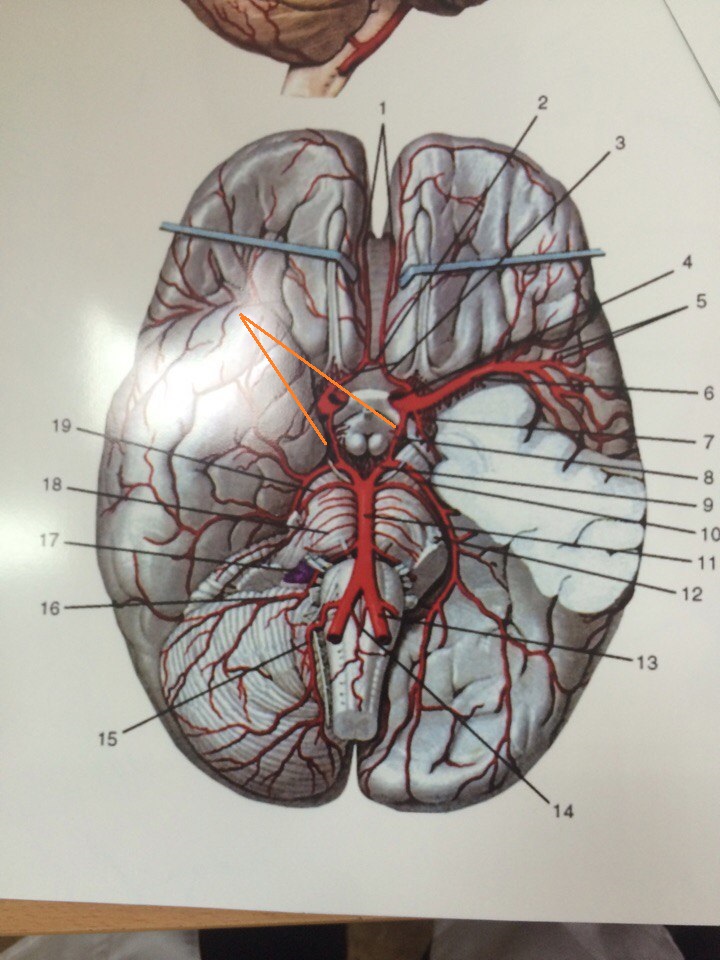

Анатомия: Задняя соединительная артерия мозга

Раздел: Фотоэссе